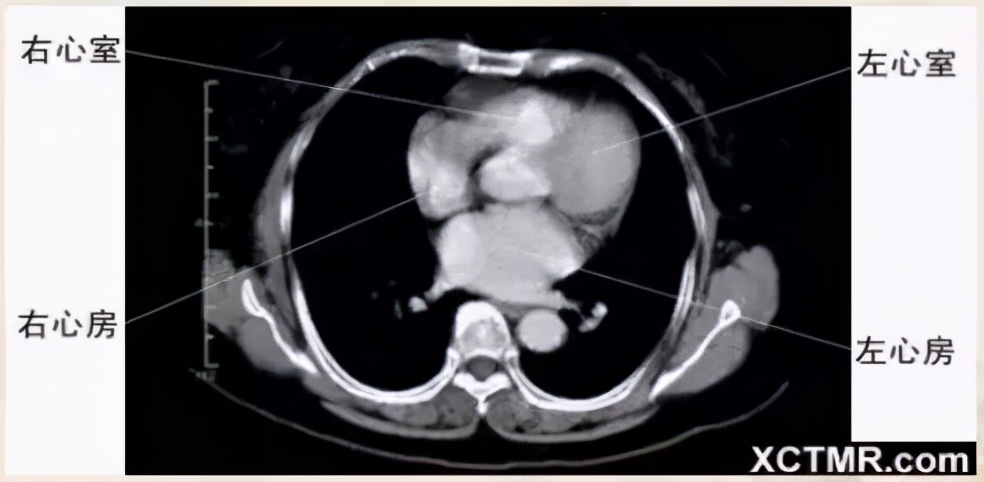

心室层面